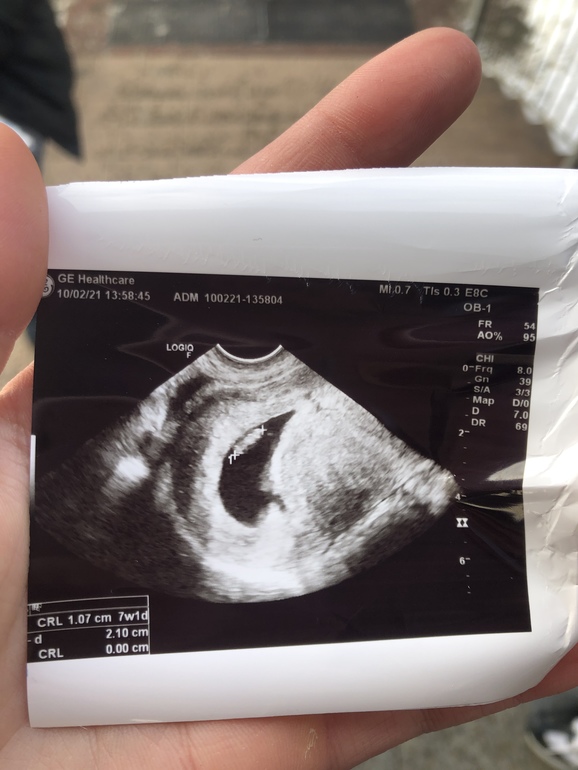

Вот мое в 6+2 тоже по Рамзи мальчик и совпало

16.11.2020